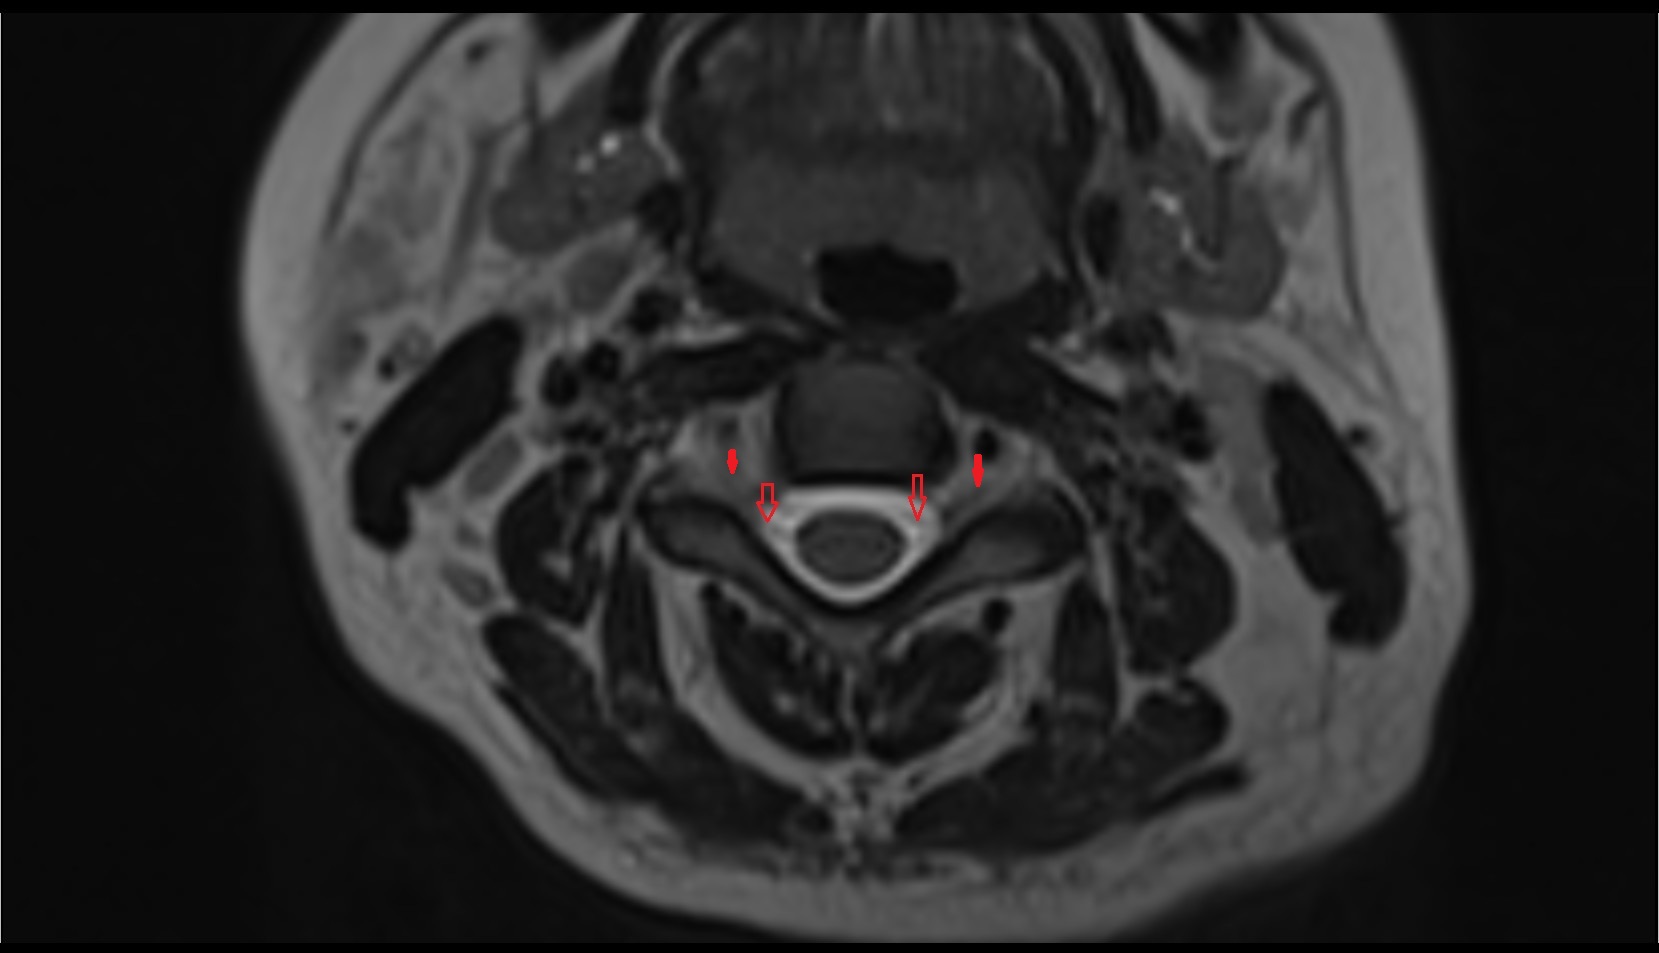

- Peripheral zone of prostate

- Anterior Fibromuscular Stroma of prostate

- Central zone of prostate

- Transitional zone of prostate